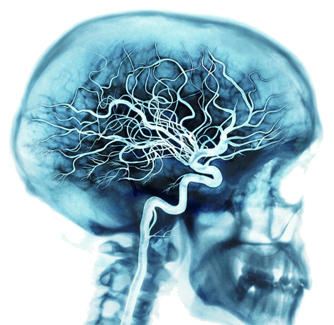

脳は、身体の最も豊かなネットワークのひとつである血管により滋養分を与えられています。

心臓が鼓動するごとに、動脈が血液の約20‐25パーセントを脳に運びます。脳では、数十億の細胞が酸素の約20パーセントと血が運んでくる燃料を消費します。

真剣に考えているとき、脳は、燃料と酸素を最高50パーセント使用します。

全身の血管網は、動脈の他に、静脈と毛細血管で構成されます。